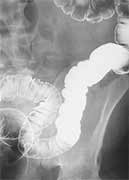

With the patients in question, their cancer has spread from the intestines to other organs such as the liver or lung, in a process called metastasis. In many cases, the prognosis is death, one expert not part of the study said.

In the study, researchers examined a database on more than 64,000 patients diagnosed with stage 4 colon or rectal cancer between 1988 and 2010.

The study reports that about two-thirds of patients underwent removal of the primary tumor, but the procedure became less common over time, dropping from 75 percent of cases in 1988 to 57 percent of cases in 2010.